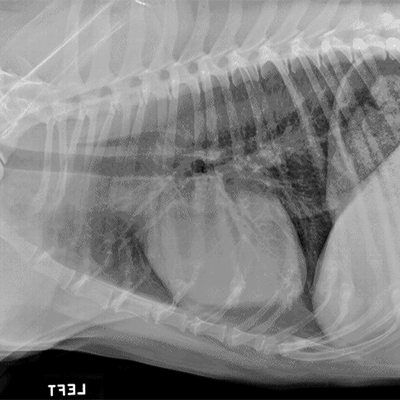

What view is this radiograph an example of?

Lateral Thorax